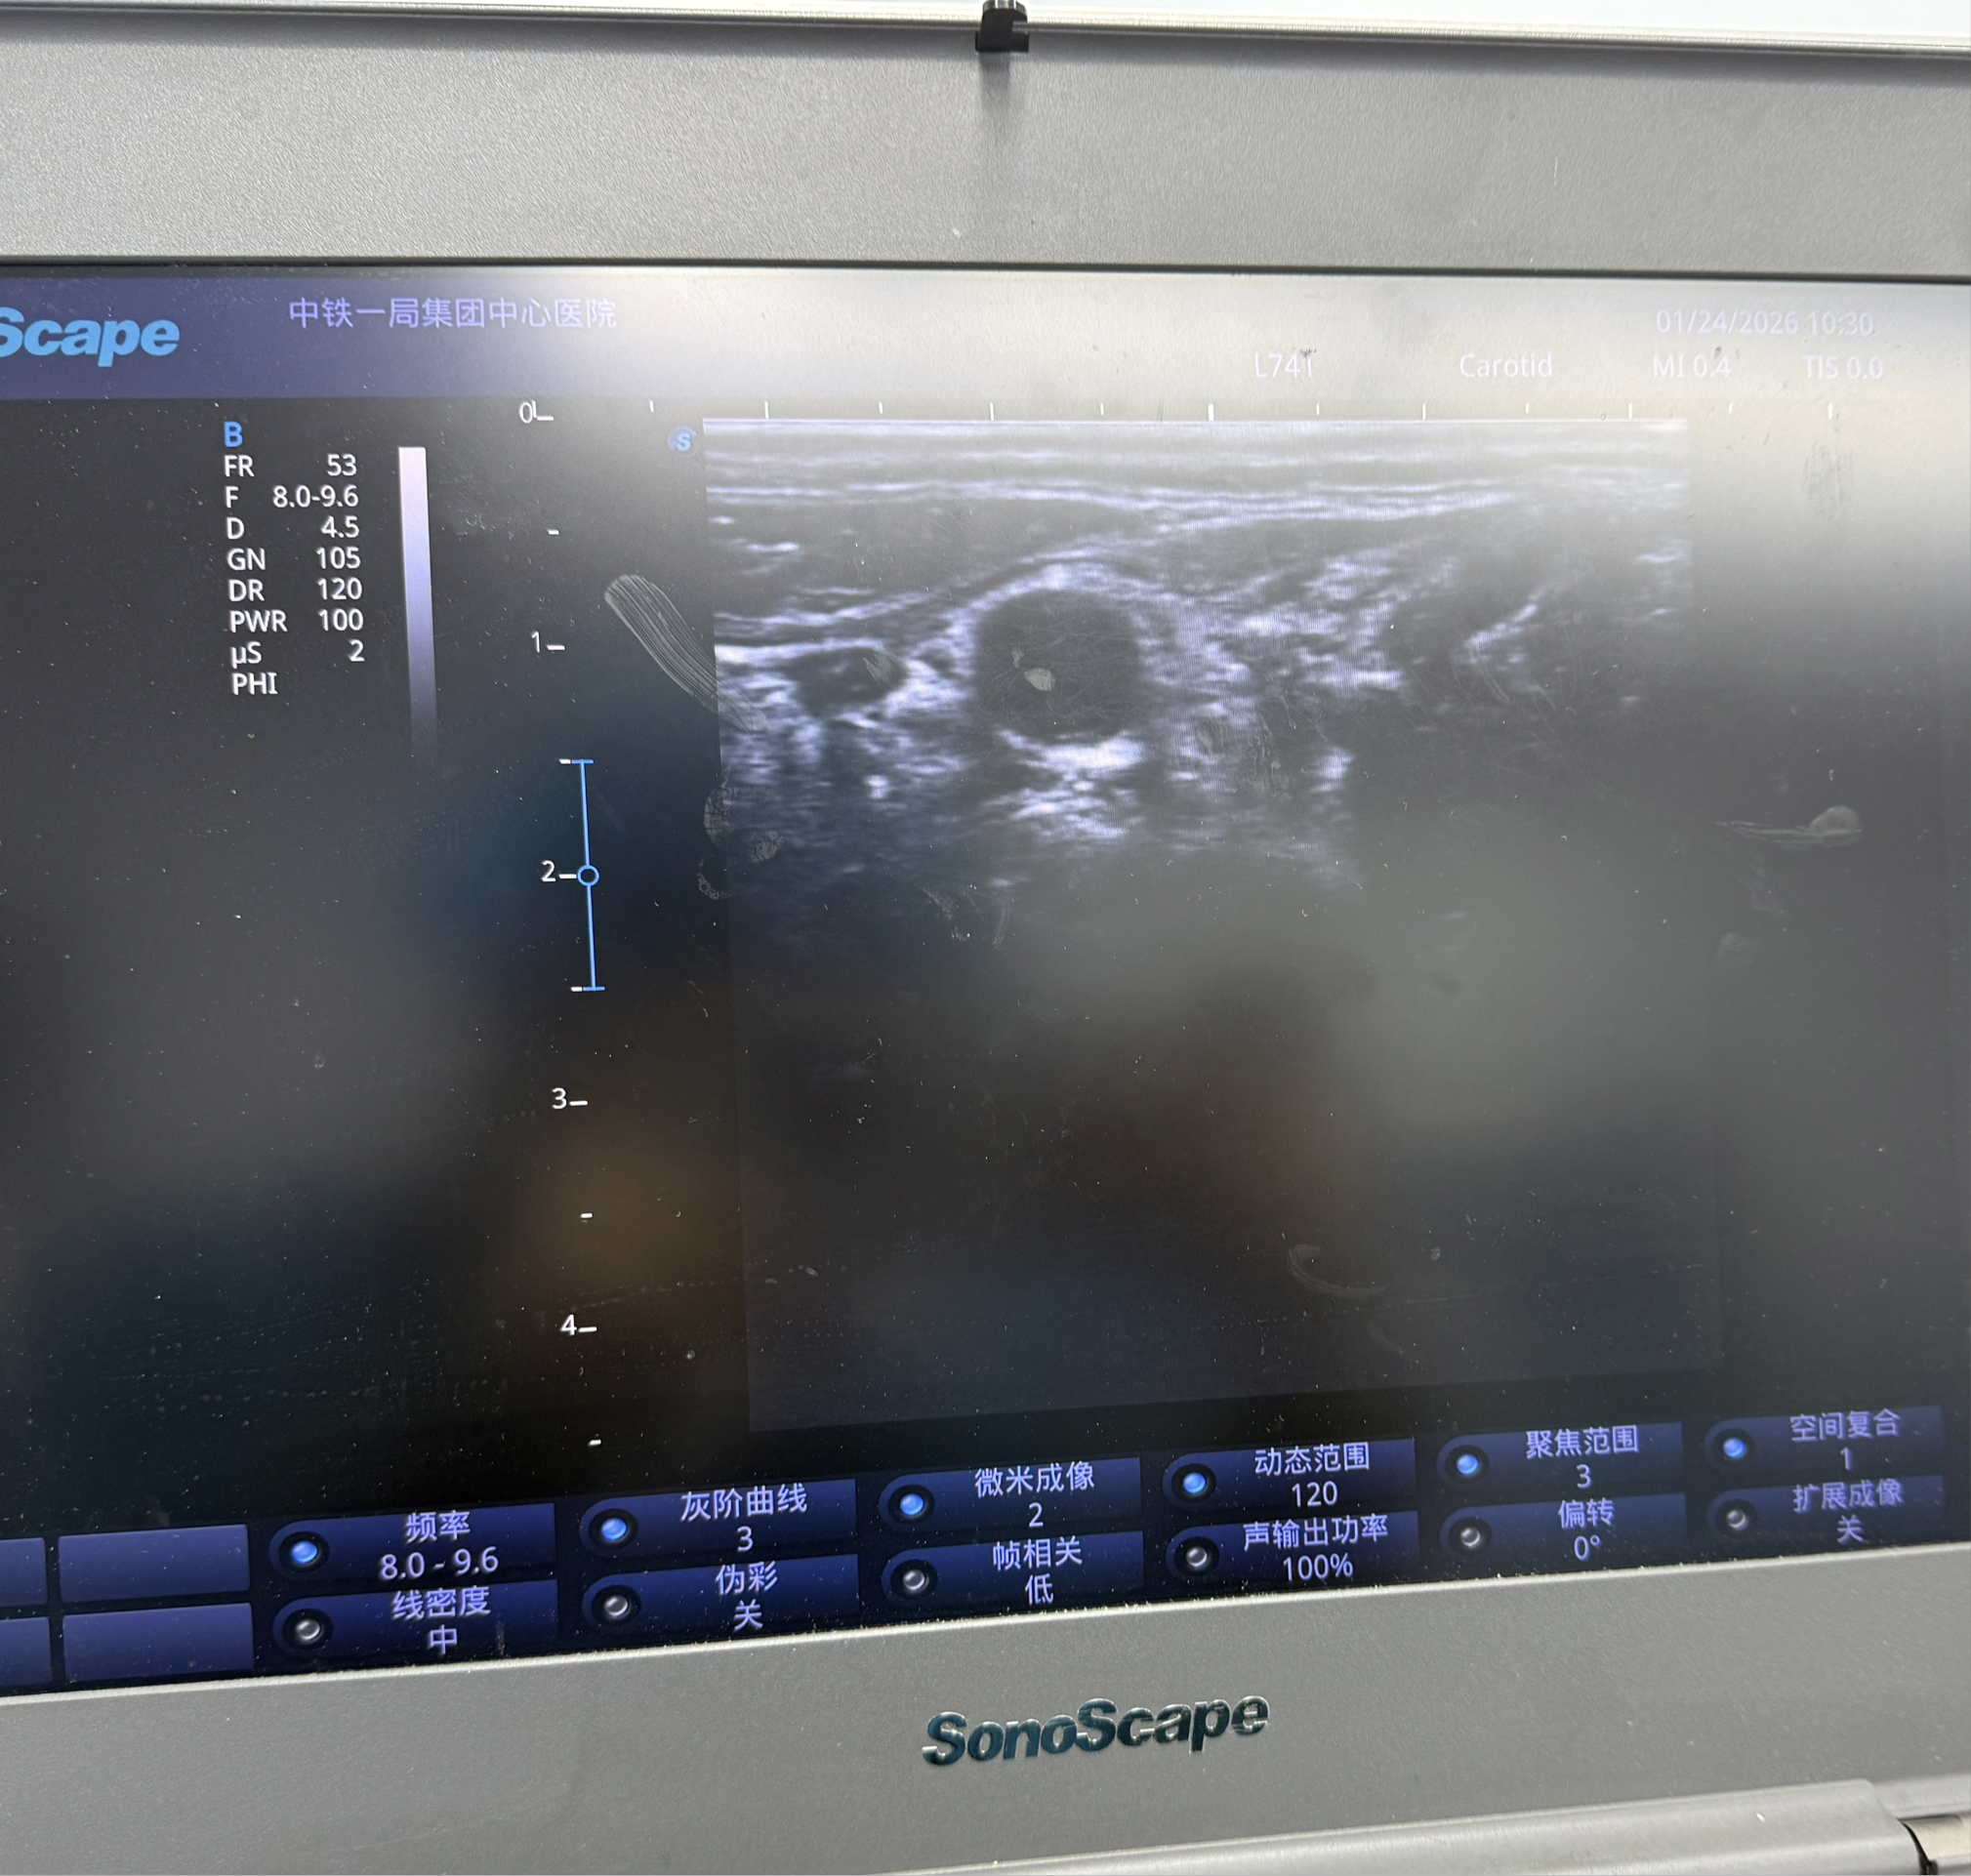

可视化操作:常规采用超声引导进行穿刺,实时显示颈部血管、神经及穿刺针位置,极大提高了操作的安全性和准确性,有效避免了传统盲穿可能引起的并发症(如血管损伤、气胸、喉返神经阻滞等)。